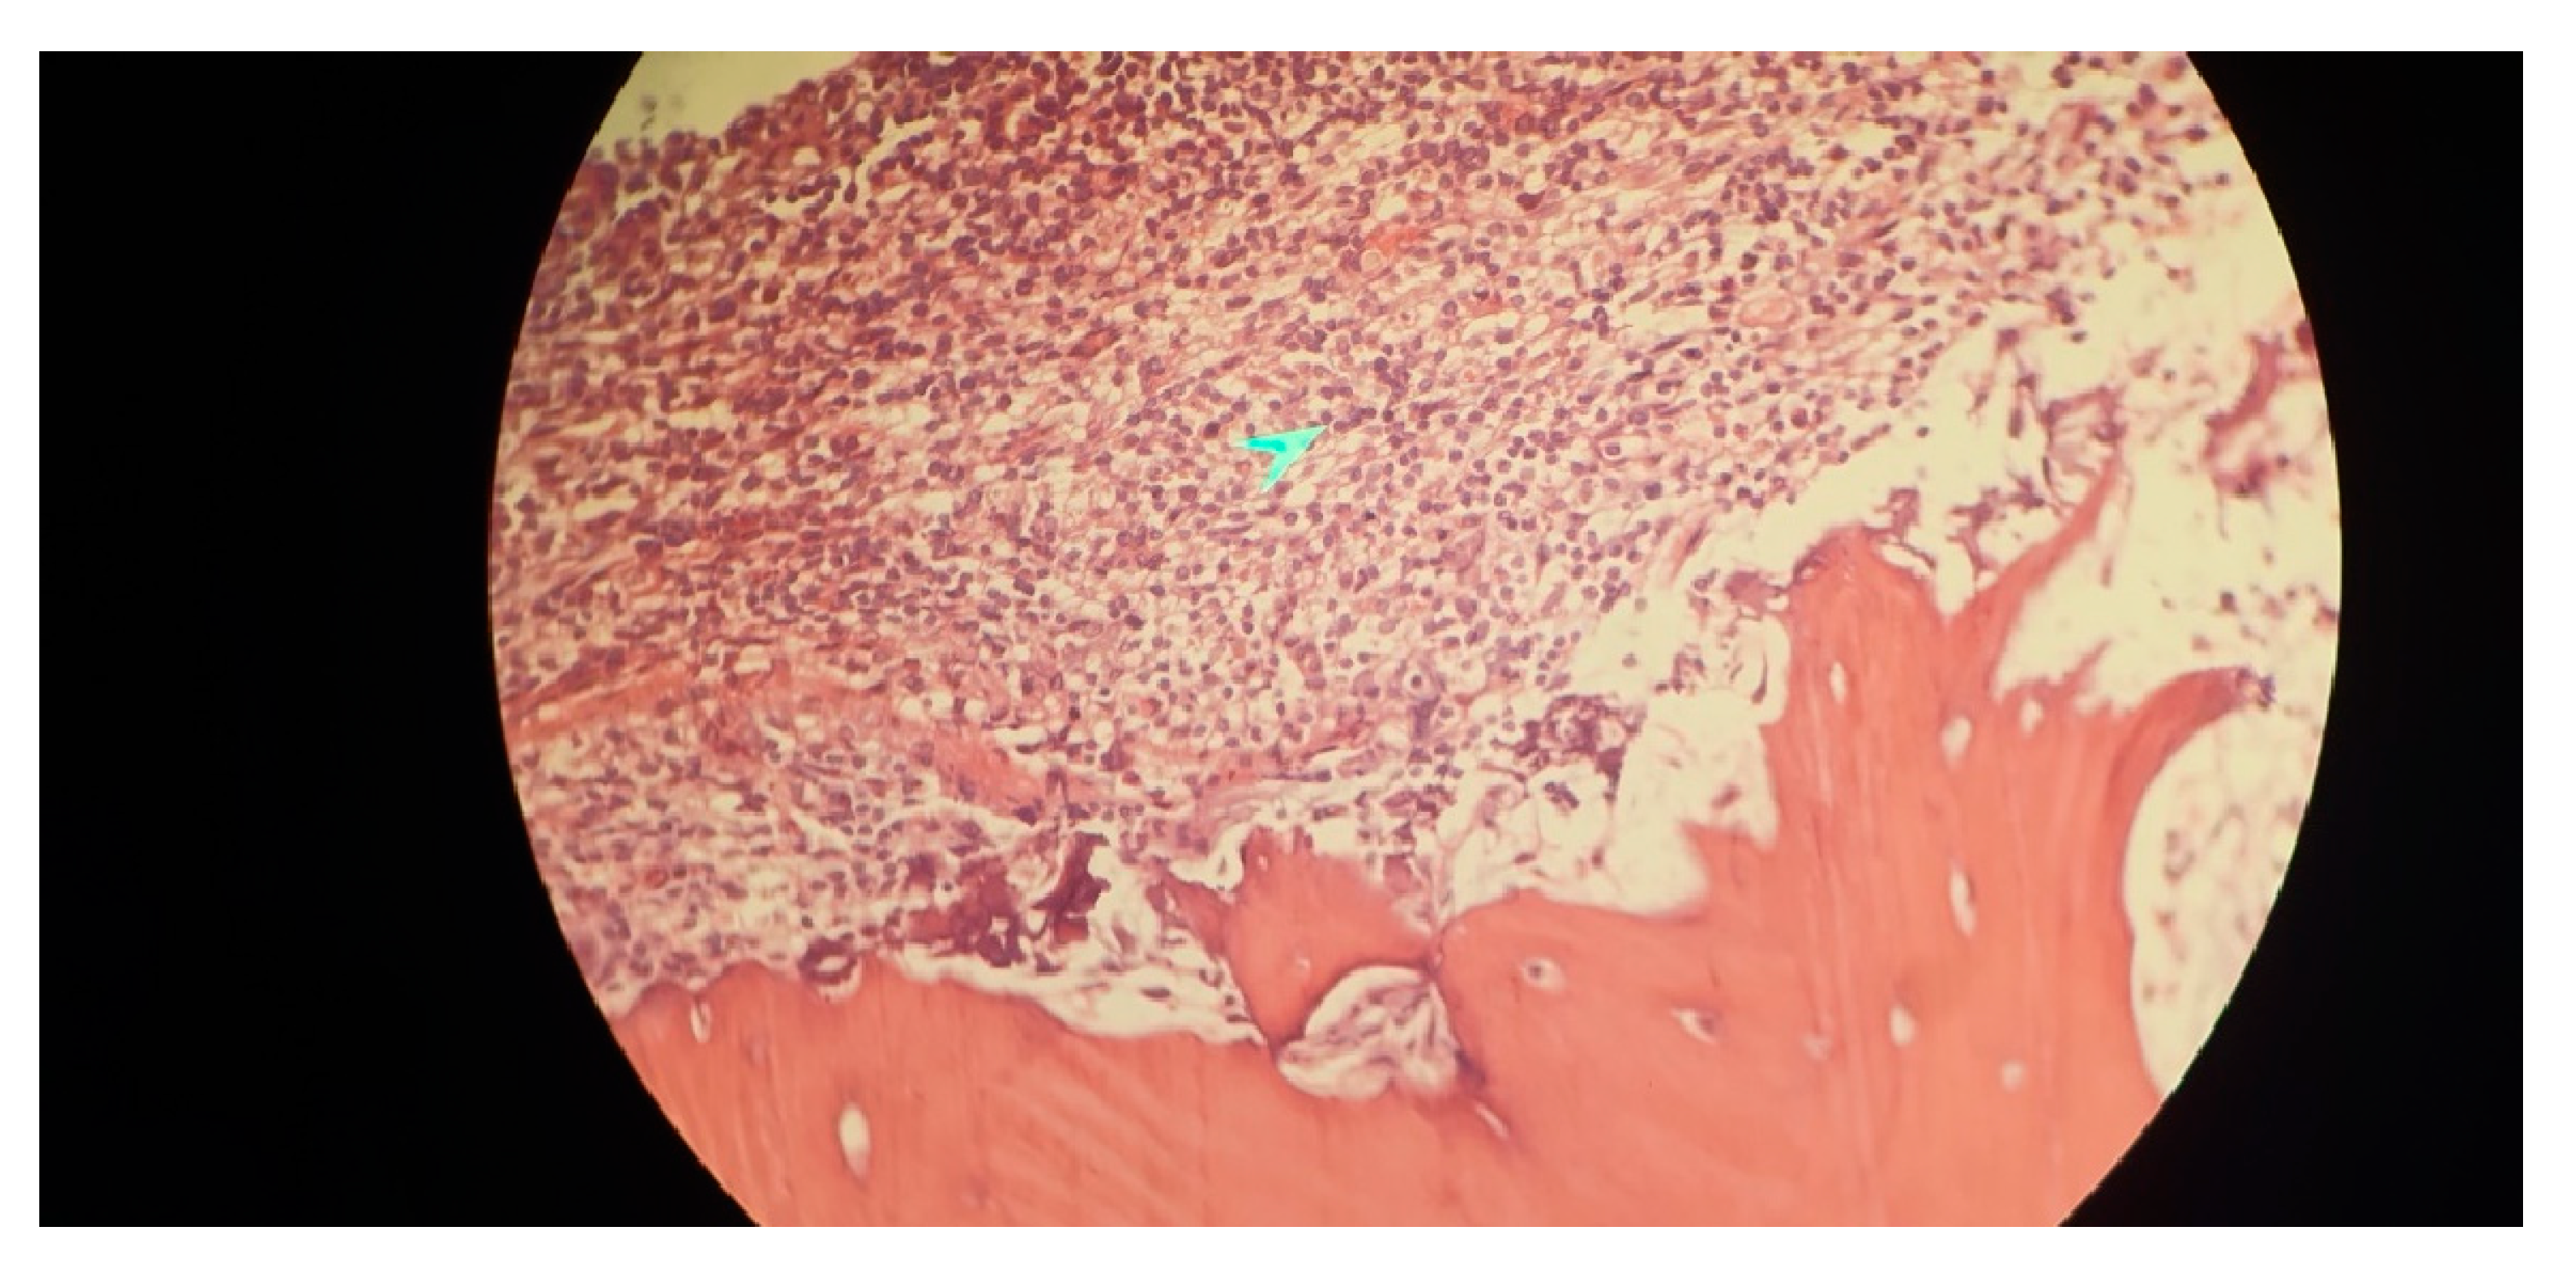

Immunophenotyping results of bone marrow aspiration by flow cytometry revealed a lymphoid cell population of about 52% of the total cell analyzed, mostly composed of mature B cells that express CD45-CD19- CD20-CD22 - surface kappa light chain and negative for CD5- CD10- CD11c-CD23-CD25- CD103-FMC7-CD34-TdT and T cell markers. Bone marrow biopsy showed fragments of bone trabecula and marrow spaces with about 70% cellularity, megakaryocytes were decreased, and no granuloma was identified. Hematopoietic elements were replaced by neoplastic lymphoid cells having round nuclei and clear cytoplasm arranged diffusely, all of which suggested marginal B cell lymphoma as the ultimate diagnosis (Figure 3).

Figure 3. Immunohistopathological evaluation bone marrow aspiration and biopsy of a 41-year-old male case of systemic lupus erythematous and antiphospholipid syndrome demonstrating fragments of bone trabecula and marrow spaces with about 70% cellularity, and hematopoietic elements replaced by neoplastic lymphoid cells having round nuclei and clear cytoplasm arranged diffusely, in favor of B-cell lymphoma. The arrow shows the neoplastic lymphoid cells arranged diffusely in marrow aspiration slides.